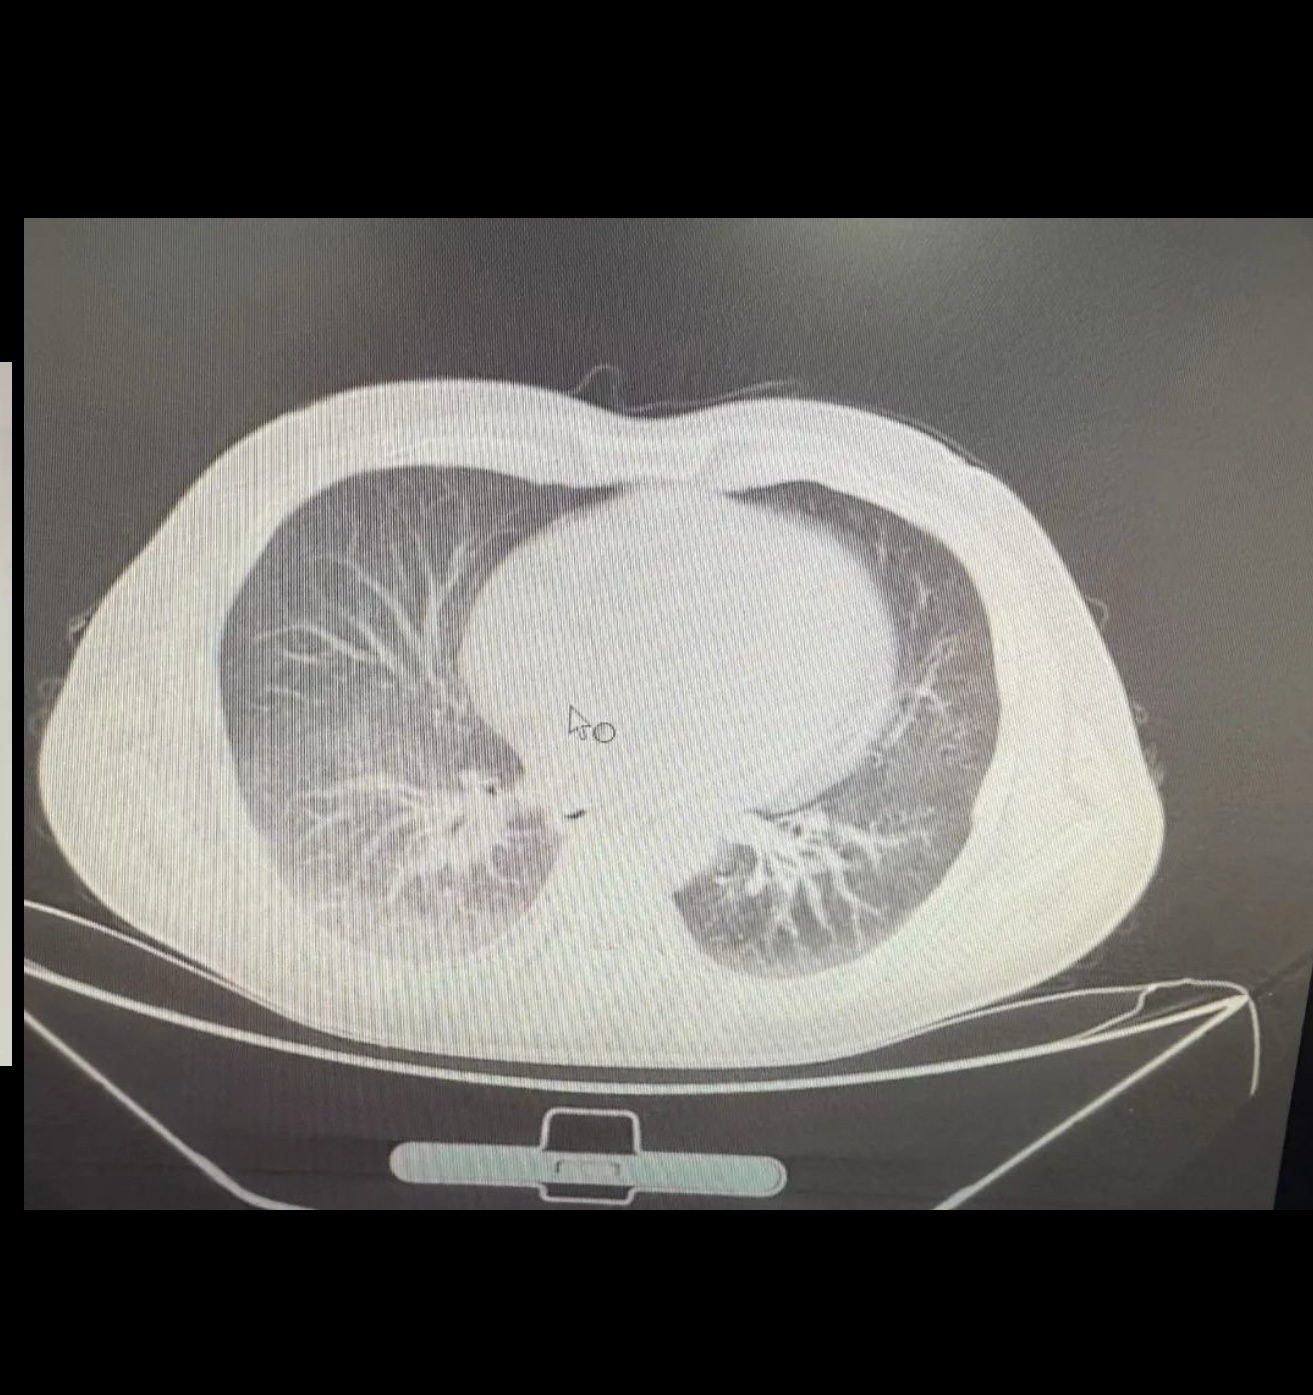

胸部ct :右肺下叶炎性改变,与7.6日对比病变已吸收;